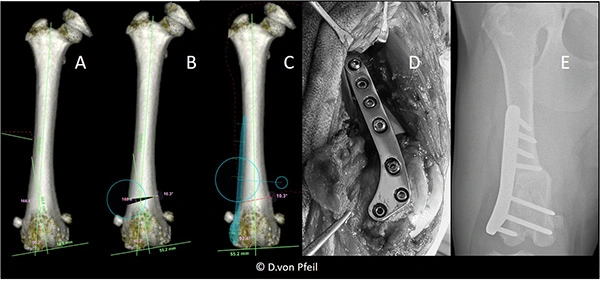

Computertomographie zur Beurteilung einer abnormen distalen Femurwinkelung, dem unteren Teil des Oberschenkels (A) die zur Luxation der Kniescheibe (Patella) führte, und Planung der korrigierenden Operation (B,C). Intraoperative Ansicht (D) und Röntgenbild nach der Operation (E). Nach der Operation ist der Oberschenkelknochen gerade ist und die Kniescheibe stabil.